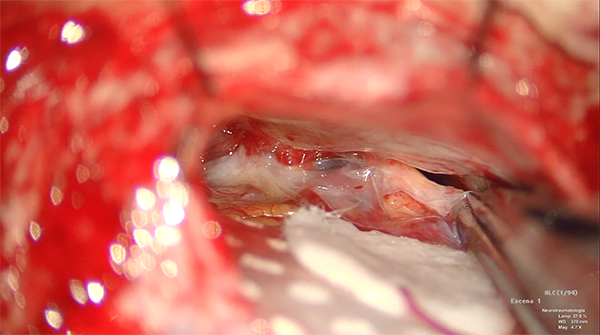

Introducción: Los aneurismas cerebrales de la circulación posterior, representan solo del 8 al 10 % del total de los aneurismas cerebrales, y de estos los de la arteria cerebelosa anteroinferior (AICA) son muy poco frecuentes, por lo que no hay algoritmo de manejo para estas lesiones, se requieren conocimientos anatómicos de vascular y de base de cráneo para el tratamiento de estos, hablando del abordaje quirúrgico, podemos mencionar, el extremo lateral, retrosigmoideo, orbitozigomatico y presigmoideo, que depende del tamaño y localización del aneurisma, ya sea distal o proximal. Presentamos este caso, que tratamos mediante un abordaje retrosigmoideo convencional, el cual nos ofreció un corredor quirúrgico suficiente, sin necesidad de un abordaje mas amplio, en este caso fue un aneurisma distal de la AICA, localizado en el segmento meatal, que se encontró en el complejo neurovascular medio del ángulo pontocerebeloso, muy próximo a los nervios craneales V, VII y VIII.

Los autores presentan en formato de video un caso titulado “Abordaje retrosigmoideo para clipaje de aneurisma distal de la AICA”. El video comienza con la descripción anatómica de la arteria AICA, detallando los segmentos y sus relaciones con la protuberancia y los pares craneanos regionales apoyados en un adecuado dibujo propio de los autores, luego la presentación clínica del caso y finalmente un video de alta resolución con los gestos quirúrgicos hasta el clipado del aneurisma, una TAC postoperatoria y fotos de la paciente. Se destaca la disección aracnoidea aguda comenzando desde las cisternas basales, cerebelo-pontina inferior y superior, luego un clipado transitorio de la AICA proximal al aneurisma para poder completar la disección y clipado definitivo. Hay varios tips para mejorar el video, durante el proceso de clipado la cabeza de la pinza clipera ocultó la visión de las patas del clip lo cual no se pudo apreciar correctamente el posicionamiento y liberación (seguramente el cirujano lo vio perfectamente no así la cámara de video), luego del clipado no se mostró detalladamente la exploración de la AICA, el cuello y el posicionamiento del clip. Nosotros en general punzamos el aneurisma luego del clipado, lo coagulamos y así se aumenta la visión para la exploración regional del cuello clipado; otro complemento muy útil es el verde de indocianina para realizar el ICG videoangiografía, seguramente los autores no lo tienen disponible. Tampoco se mostró al final del video una angioTAC o angiografía digital cerebral postoperatoria.

Los autores presentan de manera elegante la resolución quirúrgica de un aneurisma de la arteria cerebelosa antero inferior (AICA) derecha de variante distal, patología de muy baja incidencia. Se incluye un breve correlato anatómico, la presentación del cuadro y las imágenes pre e intraoperatorias de alta calidad.

Es importante, como se puntualiza en el video, que el abordaje sea lo mas amplio posible, exponiendo la emergencia de los pares bajos, con apertura de la cisterna magna para obtener una porgresiva relajacion del cerebelo, a fin de disecar extensivamente las adherencias de las estructuras neurovasculares del ángulo pontocerebeloso, lo cual redundara en disponer de múltiples ángulos de ataque una vez expuesta la malformación.